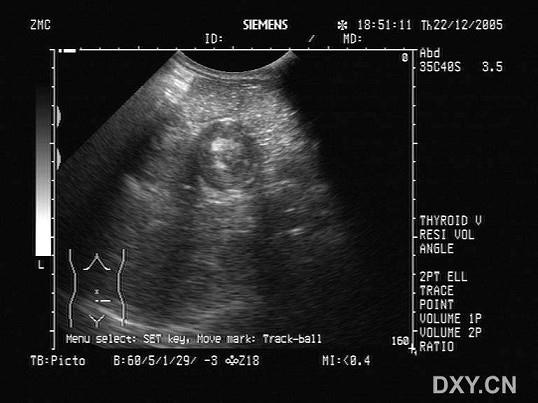

患者腹痛3小时,超声检查左下腹显像如图,诊断可能为?(?)A.肠道扩张B.肠道肿瘤C.肠套叠D.肠道蛔虫症E.肠结核

问题 患者腹痛3小时,超声检查左下腹显像如图,诊断可能为?(?)

选项 A.肠道扩张 B.肠道肿瘤 C.肠套叠 D.肠道蛔虫症 E.肠结核

答案 C